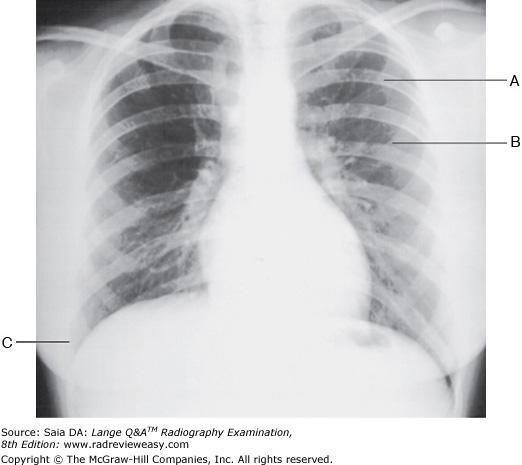

The PA chest radiograph shown in the figure below demonstrates

1. rotation

2. scapula superimposed on lung fields

3.

adequate inspiration

1, 2, and 3

Which of the following statements with respect to the PA chest seen in Figure 2–11 is (are) correct?

- Adequate inspiration is demonstrated.

- The shoulders are rolled forward adequately.

- Rotation is demonstrated.